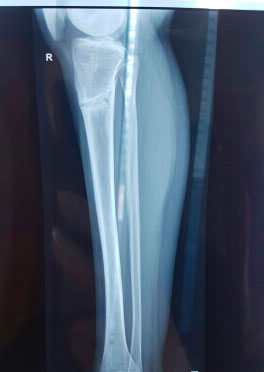

Дата операции - 12.10.2017г.

Дата снятия аппаратов 22.01.2018г.

Срок лечения 100 дней.